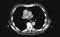

CT of a pulmonary tumor CT of right and left pulmonary arteries 3. Remove the lungs. (Play movie; View images: N 199, 206, 209, 232, TG 4-31, 4-35, 4-36, 4-38)